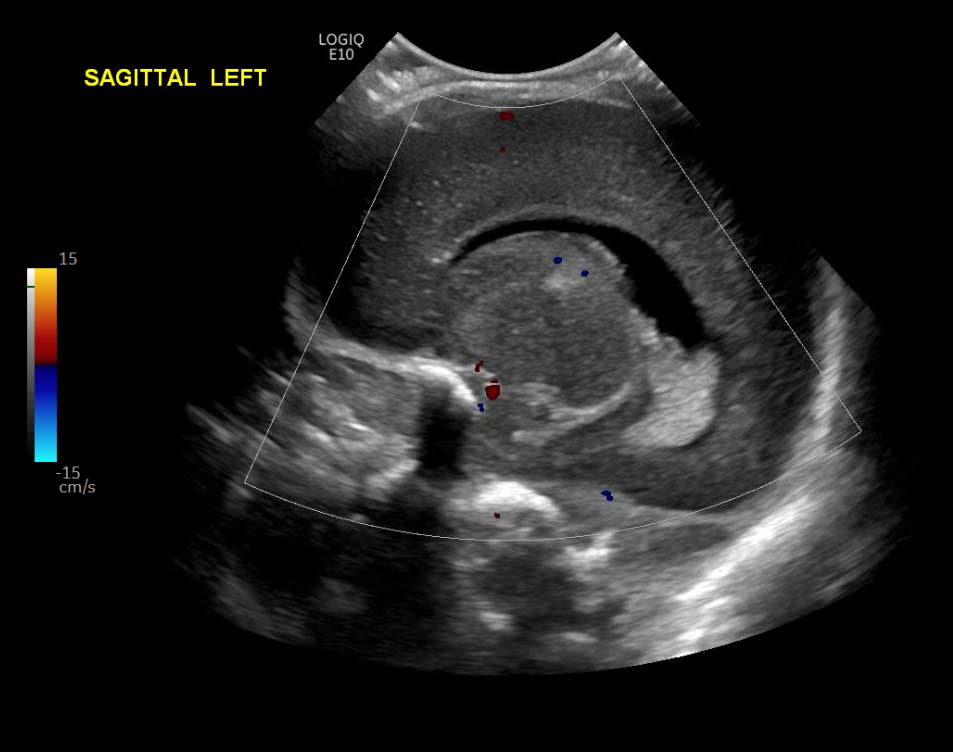

Indication: Evaluate for germinal matrix hemorrhage

Grade 2 germinal matrix hemorrhage

Sample ReportLeft germinal matrix hemorrhage involving the caudothalamic groove and layering in the occipital horn of the left lateral ventricle without hydrocephalus (grade 2).

No abnormal brain parenchymal echogenicity or extra-axial collections.

Premature sulcation pattern.